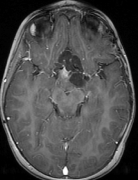

Note that term 2 is sparse if there are no major changes between and , both images have similar grey-level intensities and they are spatially matched. While these conditions meet in many application of dynamic imaging, such as prior image constrained compressed sensing (PICCS) in CT (Chen et al., 2008; Lauzier et al., 2012) and dynamic MRI (Jung et al., 2009; Lustig et al., 2006; Gamper et al., 2008; Yip et al., 2014), in longitudinal MRI none of these requirements are guaranteed. While there are solutions for miss-registration and variable grey level intensities (see Section 4), the temporal similarity in longitudinal MRI is a-priori unknown. Although longitudinal MRI may exhibit temporal similarity (Samsonov et al., 2010), we have to take into account that in many cases the follow-up scan may exhibit substantial changes with respect to the baseline scan. Such cases may occur, for example, if a surgical intervention was applied between the time points or if there is a major progressive or therapy response. Figure 2 shows two representative examples.

Baseline 4 months Baseline 3 months

Hydrocephalus GBM